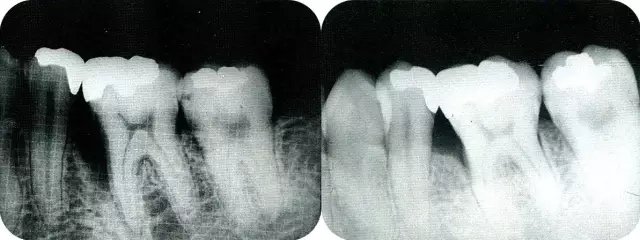

▲圖7-7  術(shù)前,術(shù)后的x片。確認(rèn)出現(xiàn)骨再生,牙槽嵴硬線。